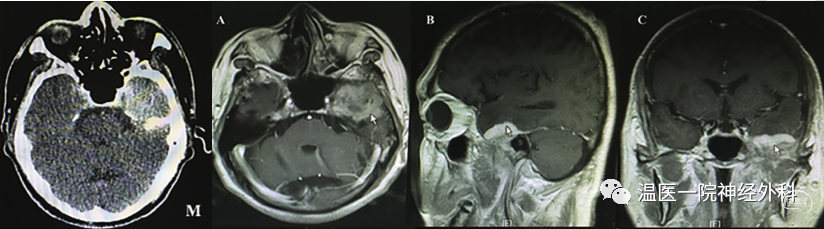

目前对于RDD的治疗及随访流程(图4)推荐如下[6][7]:

1.对于局灶性病变(图4左),若无明显临床症状,可考虑随访或手术切除;若有明显临床症状,则倾向于尽可能手术全切,进一步地,对于术后有残留而无症状者可考虑继续随访,对于术后有残留而有症状者则可考虑放疗,而对于放疗后症状仍有进行性加重的则考虑激素、干扰素等药物治疗。

2.对于全身性病变(图4右),若无明显临床症状,同样可考虑随访或手术切除;若有明显临床症状,则倾向于激素、干扰素等药物治疗。